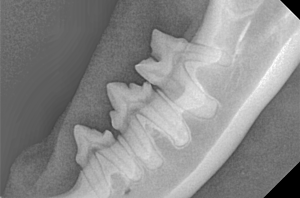

Canine Full Mouth Radiograph Example